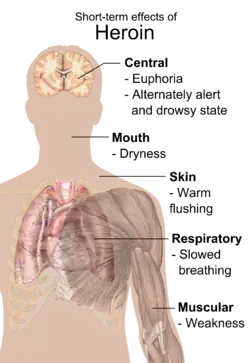

Short-term effects

Users report an intense rush, an acute transcendent state of euphoria, which occurs while diamorphine is being metabolized into 6-monoacetylmorphine (6-MAM) and morphine in the brain. Some believe that heroin produces more euphoria than other opioids; one possible explanation is the presence of 6-monoacetylmorphine, a metabolite unique to heroin – although a more likely explanation is the rapidity of onset. While other opioids of recreational use produce only morphine, heroin also leaves 6-MAM, also a psycho-active metabolite.

The rush is usually accompanied by a warm flushing of the skin, dry mouth, and a heavy feeling in the extremities. Nausea, vomiting, and severe itching may also occur. After the initial effects, users usually will be drowsy for several hours; mental function is clouded; heart function slows, and breathing is also severely slowed, sometimes enough to be life-threatening. Slowed breathing can also lead to coma and permanent brain damage.[61] Heroin use has also been associated with myocardial infarction.[62]